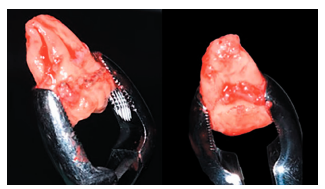

Se procedió entonces a la extracción del 2.8 con fórceps (Figura 8), manipulando mínimamente el ligamento periodontal del tercer molar, colocando el tercer molar superior en la posición del primer molar superior (Figuras 9 y 10).